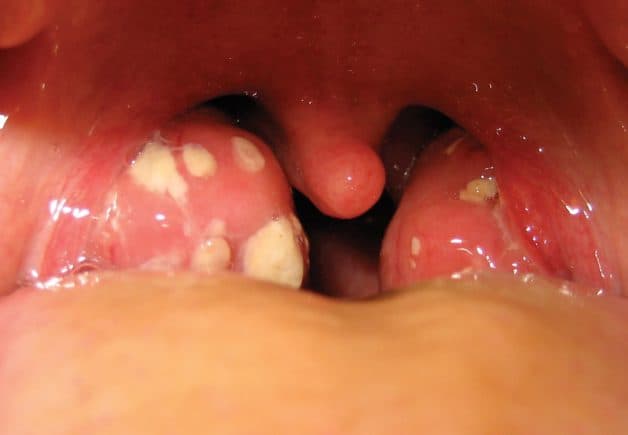

– Khi quan sát sẽ thấy amidan bị sưng, phù nề và có thể có bựa trắng.

– Amidan có nhiều ngóc ngách chứa các hốc mủ bã đậu, tạo điều kiện thuận lợi cho vi khuẩn sinh sôi và phát triển.